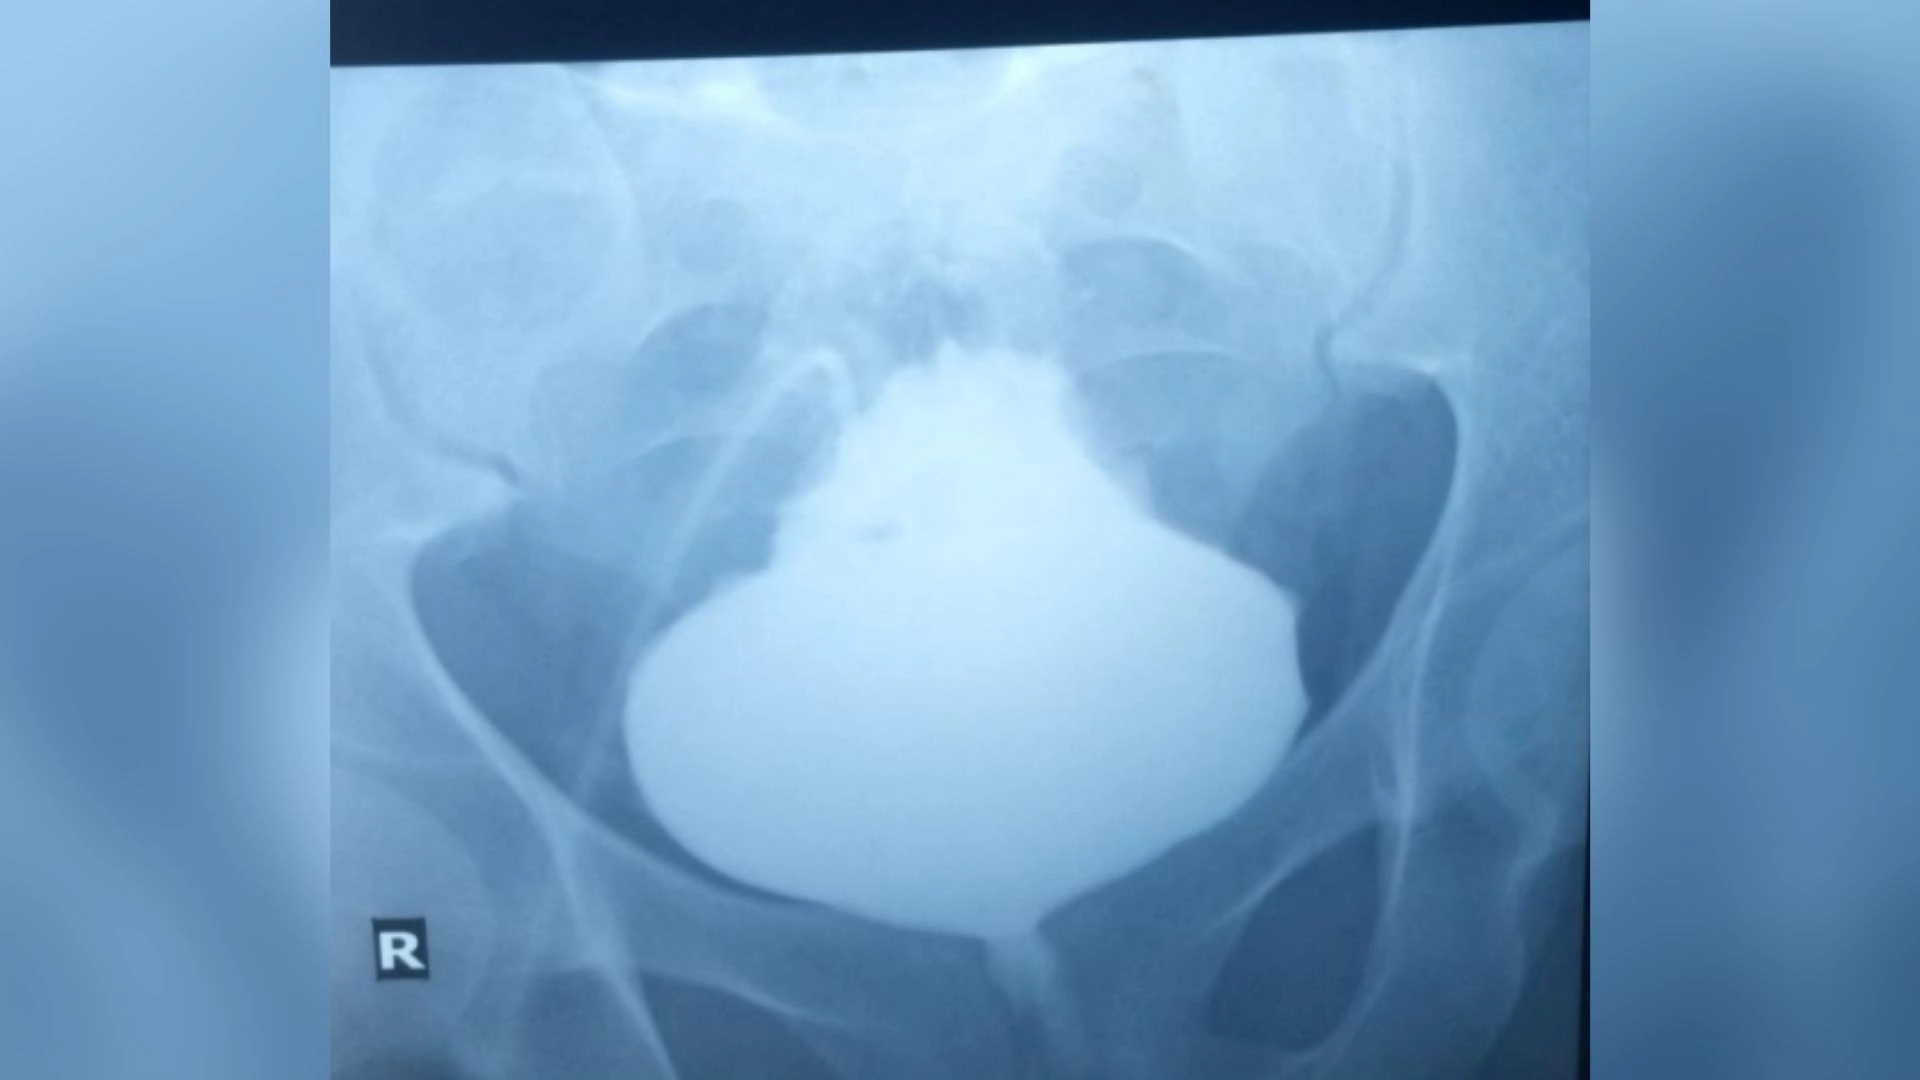

The doctors referred the patient to the radiology department to get scans of his bladder and search for signs of such physical abnormalities. To visualize the bladder in X-ray scans, the radiologists administered an X-ray-sensitive dye through the abdominal catheter. This revealed that the bladder had inflated at its base, leaving a pointy tip.

The diagnosis: This condition is known as a "Christmas tree" or "pinecone" bladder, owing to its appearance.

The X-rays confirmed that urine had been blocked from leaving the organ. Yet a closer inspection of the bladder revealed no issues with the organ itself, such as an obstructing mass or bladder stones. This led the doctors to wonder if an obstruction was located elsewhere.